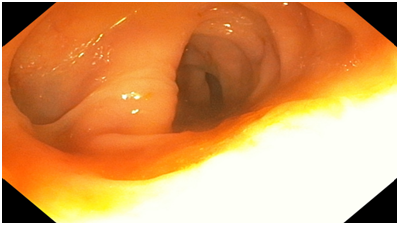

Figure 3 An endoscopic image of the Transverse colon showing normal appearance.